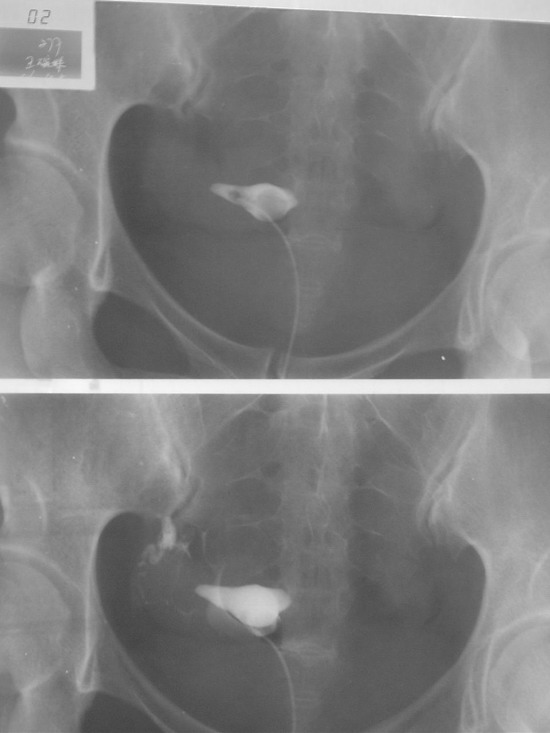

输卵管造影检查过程图片

输卵管造影成影图片

输卵管造影X光图片